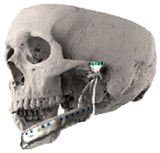

| 1 | 71 | FT-M0 | ![]() | Temporal bone, aygomatic arch, glenoid fossa and condyle | Unalloyed titanium mesh temporal and zygomatic backing capping the UHMWPE fossa | Cobalt-chromiun-molybdenum alloy condylar head and Titanium alloy body | Skull component: 62.0 mm titanium screws. Manibular component: 82.7 mm titanium screws |

| 2 | 58 | FA-M0 | ![]() | Glenoid fossa with medial extension and condyle | Alloyed titanium backing capping the UHMWPE fossa | Cobalt-chromiun-molybdenum alloy condylar head and Titanium alloy body | Skull component: 52.0 mm titanium screws. Manibular component: 82.7 mm titanium screws |

| 3 | 41 | FO-M3 * | ![]() | Glenoid fossa and complete left hemimandible | Alloyed titanium backing capping the UHMWPE fossa | Cobalt-chromiun-molybdenum alloy condylar head and Titanium alloy body consisting of two interloching pieces | Skull component: 52.0 mm titanium screws. Manibular component: 112.7 mm titanium screws |

| 4 | 71 | FA-M3 | ![]() | Left zygomatic arch, glenoid fossa and complete left hemimandible extended to the right hemimandible ramus | Alloyed titanium zygomatic backing capping the UHMWPE fossa | Titantium alloy | Skull component: 82.3 mm titanium screws. Manibular component: 62.7 mm titanium screws |

| 5 | 26 | FA-M0 | ![]() | Temporal bone, zygomatic arch, glenoid fossa and condyle bilatreally | Alloyed titanium zygomatic backing capping the UHMWPE fossa | Cobalt-chromiun-molybdenum alloy condylar head and Titanium alloy body | Skull component: 172.0 mm titanium screws. Manibular component: 192.7 mm titanium screws |

| 6 | 54 | F0-M2 | ![]() | Glenoid fossa and complete right hemimandible | Alloyed titanium backing capping the UHMWPE fossa | Cobalt-chromiun-molybdenum alloy condylar head and Titanium alloy mesh body | Skull component: 52.3 mm titanium screws. Manibular component: 92.7 mm titanium screws |

| 7 | 63 | F0-M3 | ![]() | Glenoid fossa and complete left hemimandible | Alloyed titanium backing capping the UHMWPE fossa | Cobalt-chromiun-molybdenum alloy | Skull component: 52.3 mm titanium screws. Manibular component: 82.7 mm titanium screws |

| 8 | 24 | F0-M3 * | ![]() | Glenoid fossa and complete right hemimandible extended to the left hemimandible ramus | Cobalt-chromium-molybdenum alloy backing capping the UHMWPE fossa | Cobalt-chromiun-molybdenum alloy | Skull component: 52.3 mm titanium screws. Manibular component: 112.7 mm titanium screws |

| 9 | 52 | FT-M0 | ![]() | Temporal bone, zygomatic arch, glenoid fossa extended medially and condyle | Cobalt-chromium-molybdenum alloy backing capping the UHMWPE fossa | Cobalt-chromiun-molybdenum alloy | Skull component: 82.3 mm titanium screws. Manibular component: 82.7 mm titanium screws |